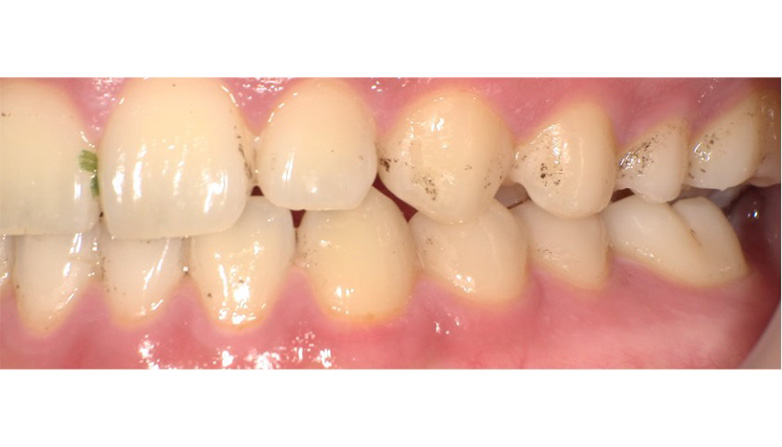

症例4

before

after

| 主 訴 | 着色を落としたい |

| 治療期間 | 通院 1回 |

| 治 療 費 | 1回 11,000円(税込) |

| 治療内容 | PMTC+エアフロー |

| 治療のリスク | 歯自体の色を白くすることはできない。 生活習慣によってはしばらくすると再び着色することがある。 術後、しみることが稀にある。 |